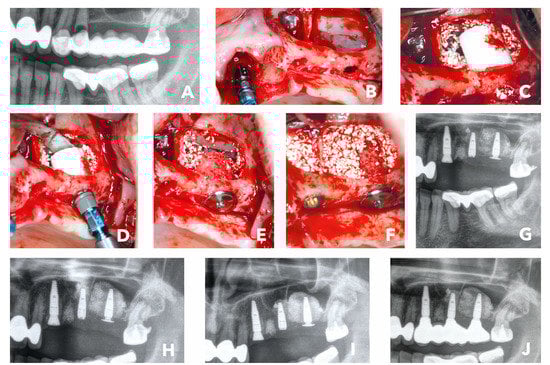

A 56-year-old female patient, non-smoker without major risk factors presented with a former apiectomy in frontal maxilla. Teeth #11 and 22 had fractured roots and the areas were infected. The radiological images showed severe bone loss in the frontal maxilla (#11, #12, #21 and #22). Teeth 11 and 22 already lost two-thirds of their vertical attachment. The overdenture showed some mobility and had become symptomatic, which made removal inevitable (Figure 2A,B). The treatment plan consisted of the extraction of the endodontically treated teeth (#11, #22 and #12) and the removal of the prosthetics suprastructure. Following the surgical steps, an immediate implantation of two bone ring blocks (maxgraft® bonering Ø 7mm, botiss biomaterials, Zossen, Germany) and fixation of the blocks with dental implants (Ankylos Implant, Dentsply Sirona, York) was performed in regio #11 and #22 (Figure 2C). The defect size was initially measured with the 7-mm trephine from the maxgraft® bonering surgical kit (botiss biomaterials, Zossen, Germany) (Figure 2B). Additionally, socket preservation with gingiva graft from the tuber maxillae at #12 was performed with the goal to gain papilla through ovate pontic restoration. The site was covered with a volume-stable bovine bone substitute (cerabone®, botiss biomaterials, Zossen, Germany) and a resorbable native collagen membrane made of porcine pericardium (Jason membrane, botiss biomaterials, Zossen, Germany) (Figure 2D). The post-operative check-up showed an eventless healing and healthy soft tissue 6 months after surgery (Figure 2E). At that time, the re-entry was performed and healing abutments were placed in order to shape the gingiva. The graft appeared to be well integrated into the native bone (Figure 2F). Six weeks later, the temporary crowns were integrated, and the first esthetic results were visible only 7.5 months after surgery (Figure 2G,H). The patient was highly satisfied with the result. A radiological control at 36 months after initial surgery showed stable bone around the shoulders of the implants that indicate a mid-term esthetic outcome (Figure 2I).

Figure 2. (A) Radiological display of the bone defect in frontal maxilla #11-22. (B) maxgraft bonering surgical kit. (C) Bone augmentation with two cylindrical FDBAs and fixation with dental implants. (D) Augmentation site contoured with bovine bone substiute and covered with collagen membrane. (E) and (F) Six-month follow-up of contouring and re-entry to place gingiva formers. (G,H) Integration of prosthetic restoration 6 weeks after re-entry and 7.5 months after initial surgery. (I) Thirty-six-month radiological follow-up showed stable bone in augmented area.